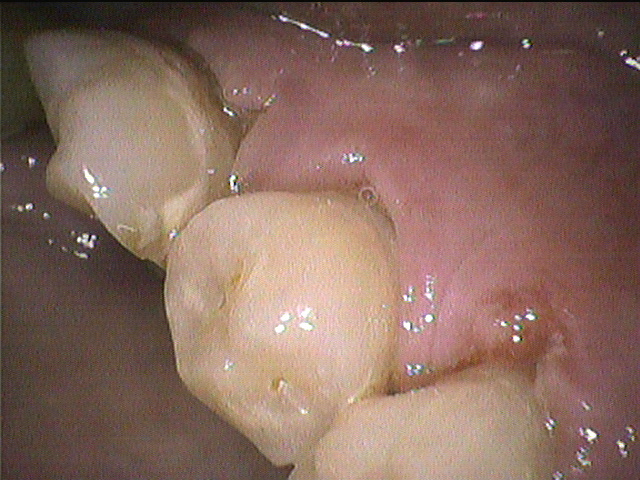

これは右下の奥歯の内側の写真です。

プラークが特に根元あたりに多く、歯ぐきは腫れていて

歯の色が白いところは少しむし歯になりかけていました。

今後穴が空いてくるようなら治療となります。

プラークをしっかり除去し、

根元に歯ブラシを当てるようブラッシング指導を行いました。